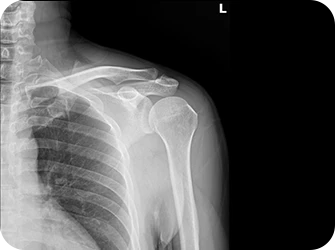

엑스레이 검사

회전근개파열

어깨와 팔을 연결하여 어깨 관절의 회전 운동을 담당하는 근육중 일부가 파열되어 팔과 어깨 통증을 발생시키는 질환으로, 중년층에게 주로 발생되며 무리한 운동으로 인한 30~40대에도 나타납니다.

원인

• 어깨를 장시간 사용할 경우

• 노화로 인한 퇴행성 변화가 있는 경우

• 어깨에 무리가 가는 운동을 한 경우

• 어깨 힘줄 사이의 염증 변화가 있는 경우

• 발육부전, 선천적 이상이 생긴 경우

• 심각한 외상에 의한 경우